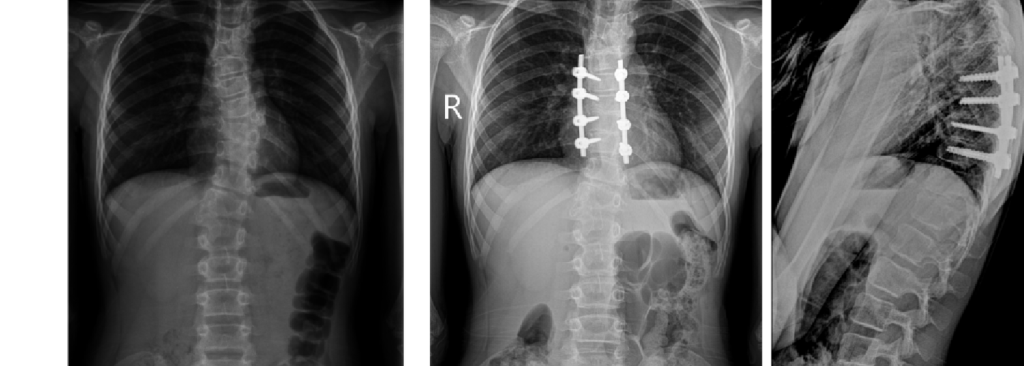

The Department is the only medical institution in the Russian Federation that performs a full range of diagnostic and therapeutic measures for children with destructive lesions of any part of the skeleton, including minimally invasive biopsies, immunological studies, histological and bacteriological verification.

The main principle of work: mandatory consideration of the child’s age characteristics and growth potential.

Technical capabilities: minimally invasive and reconstructive surgery technologies, bone plastic materials and instrumental fixation, modern power and ultrasound surgical equipment, navigation, neuromonitoring.

Main areas of surgical work: